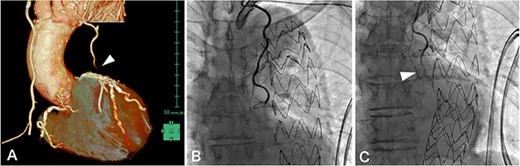

MIDCAB, harvesting of a pedicled LITA followed by an end-to-side anastomosis to the LAD with a sufficient intraoperative graft flow, was performed through left anterior mini-thoracotomy. Although the patient’s chest symptoms were vague and serum cardiac biomarkers were not elevated postoperatively, routine contrast-enhanced multi-slice CT (MSCT) on postoperative Day 3 suggested the middle of LITA graft occlusion (Fig. 1A). The following CAG also demonstrated thrombotic occlusion (Fig. 1B and C). Subsequently, we performed PCI for the lesion in the LITA graft. The lesion was crossed with a 0.014-inch guidewire (SION Blue, Asahi Intecc, Aichi, Japan); afterward, balloon dilation (Ryurei 2.0 × 20 mm, Terumo, Tokyo, Japan) was performed repeatedly. Three stents (Synergy 2.25 × 12 mm, 2.25 × 28 mm, 2.25 × 20 mm; Boston Scientific, USA) were overlappingly placed to cover the lesion, and a satisfactory angiographic result was observed (Fig. 2). The patient had an unremarkable hospital stay and remained symptom-free 2 years postoperatively.

(A) contrast-enhanced MSCT on postoperative Day 3 showing peripheral LITA graft occlusion (arrowhead); (B, C) postoperative CAG demonstrated thrombotic occlusion in the peripheral LITA graft (arrowhead), which was considered resolvable by PCI.